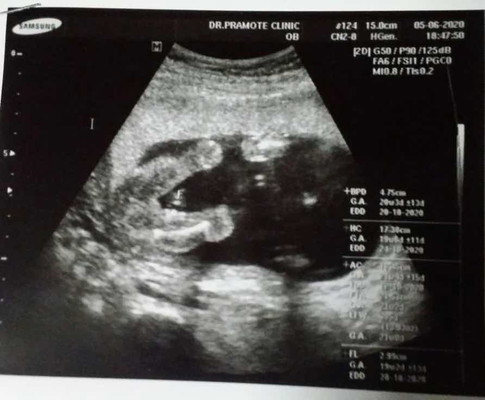

แม่ๆคะ 20+1 สัปดาห์ค่า คุณหมอบอกผู้หญิงค่า ผู้หญิงชัวร์ มั้ยคะ แม่จะซื้อของแล้ว กลัวจู๋โผล่ค่าาา ช่วยแม่คอนเฟริ์มทีค่าา ??

น่าจะผญ.นะคะ

ผู้หญิงค่ะ